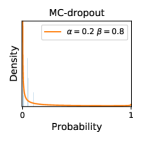

5.1 Distribution of Uncertainty Scores

Distribution of Uncertainty Scores Across Different Severity Levels As explained in Section 3, each uncertainty metric essentially defines an order/ranking among the data points. We conducted an analysis to better understand what data will be assigned high uncertainty under a particular uncertainty metric . Picking out the highest ranked data points (), we calculated the ratio of data points from each SL. Figure 4 summarizes the results as box plots for the Kaggle-DR and the Messidor-2 datasets; additional detailed statistics can be found in Table S.1 in the supplementary materials. From the plot and table, SL1 & SL2 examples account for a higher proportion among the top-ranked uncertain examples across the three ensemble methods. This finding matches our intuition that incipient disease examples (SL1 & SL2) are more likely to be considered uncertain by ensemble methods due to their ambiguity.

In contrast, the MC-dropout method showed the worst overall performance among the three, as it can be seen from the high ratios of SL0 examples among the uncertain negatives in Figure 4. The histograms in Figure 2 provides another perspective to look into the phenomenon, where a decent proportion of MC-dropout model’s predictions on SL0 inputs entailed low confidence (far from 0 or 1), which from another angle explained why MC-dropout was less specific in terms of lower FNP; many no-DR inputs (i.e. SL0) were erroneously assigned high uncertainty by MC-dropout models.

It is still an open question why the evaluated MC-dropout networks signaled relatively high uncertainty on SL0 & SL3 & SL4 data that are less likely to be ambiguous. We conjecture that much of the “uncertainty” indicated by disagreement among test-time dropout samples actually reflects the stochastic nature of dropout networks rather than the real decision uncertainty associated with the data. It is worth noting that the MC-dropout model we evaluated was not weak per se; they all achieved above Area Under Curve (AUC) scores on test sets. The weakness of individual test-time samples (which explains their low-confidence predictions on SL0 & SL3 & SL4) might have been hidden when they are aggregated into an ensemble—a well-known advantage of ensemble learning. Our results suggested that the uncertainty information given by implicit ensemble methods such as MC-dropout and TTA might not be as reliable as that from explicit ensemble approaches (e.g., stacking ensembles). Similar findings on MC-dropout can be found in some previous papers [1].

As discussed in Section 5.1 and Section 5.3 in the main paper, the mean metric and the stacking ensemble will have better performance in the precision (specificity) on the ambiguous data. Here, more detailed results are shown in Figures S.3 & S.6 and Table S.1. Figures S.3 & S.4 show the histograms of the uncertainty score for Kaggle-DR and Messidor-2 datasets that are the in-distribution (i.d.) dataset in our experiment and FigureS.5 & S.6 show the histograms for ImageNet and CIFAR-10 datasets, which is the o.o.d. datasets in our experiment. Each group of histograms contains results from the three evaluated ensemble methods (stacking ensemble, MC-dropout and TTA) and the three uncertainty metrics (mean, var and kl). Additional detailed results not displayed in Figure 4 can be found in Table S.1, which shows the proportion of the data of different SLs varies across different . For comparison, we also included in Table S.1 the results from single learners, and the proportions of data of different SLs (before any selection was made).